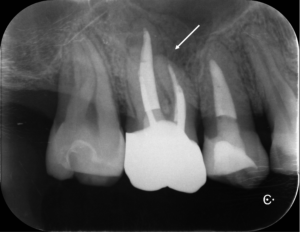

矯正の先生からは、内部吸収をしているので治してほしいと言われてたのですが、レントゲンを撮って良く見てみるとこれは外部吸収でした。

上のレントゲンを見ていただくとわかると思いますが、赤矢印の先(歯の外側から)吸収が開始され、歯の内部に吸収が向かい黄色矢印のところまで歯の内部が溶けてしまっているのです。

この病名は、ICR(Invasive Cervical Resorption)「侵襲性歯頸部外部吸収」(しんしゅうせいしけいぶがいぶきゅうしゅう)といいまして、

言葉で書くのは簡単ですが、これには非常に時間がかかりとても困難な治療でした。そこにMTAセメントを用い、根の先端の方(赤矢印)と吸収部(黄色矢印)を同時に埋めました。

黄色矢印の左の方を見ていただくとわかると思いますが、外にはみ出しているのがわかるかと思います。